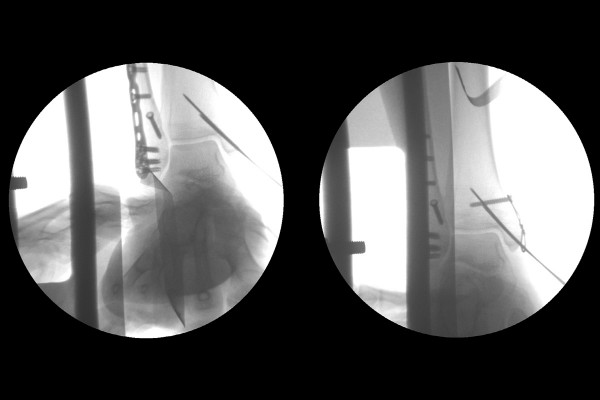

수술은 실시간 X-RAY인 C-ARM을 보면서 진행하였고, 먼저 바깥쪽 복숭아뼈를 금속판(플레이트)과 지연나사(lag screw)로 고정합니다.

골절편이 작은 안쪽 복숭아뼈(내복사)는 작은 스크류와 핀, 와이어로 고정해줍니다.

CT에서 확인되었던 뒤쪽 복숭아뼈(후복사)는 골편이 관절면 전체면적의 25프로를 넘지 않기 때문에, 뼈를 잘 맞춰주면 제자리로 들아가므로, 따로 추가적인 고정을 시행하지 않았습니다.